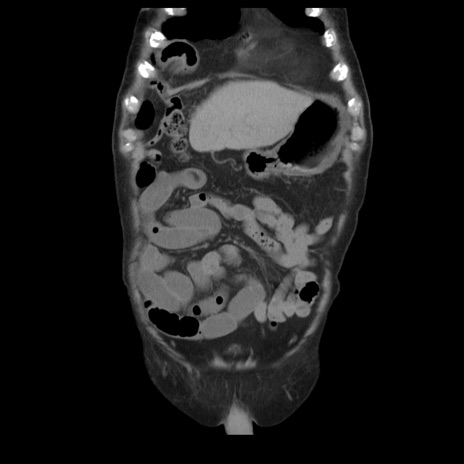

横断像

【症例】70歳代男性

【主訴】腹痛

【現病歴】肝硬変・肝細胞癌にてかかりつけの方。約9時間前に食後より腹痛出現。症状が徐々に増悪し、嘔吐出現したため来院。

【既往歴】肝硬変、肝細胞癌(RFA、TACE後)

【身体所見】意識清明、表情苦悶様、BT 36℃、BP 129/78mmHg、P 88bpm、SpO2 97%(RA)、右上腹部から心窩部にかけて圧痛あり、反跳痛なし、筋性防御あり。

【データ】WBC 5800、CRP 0.16